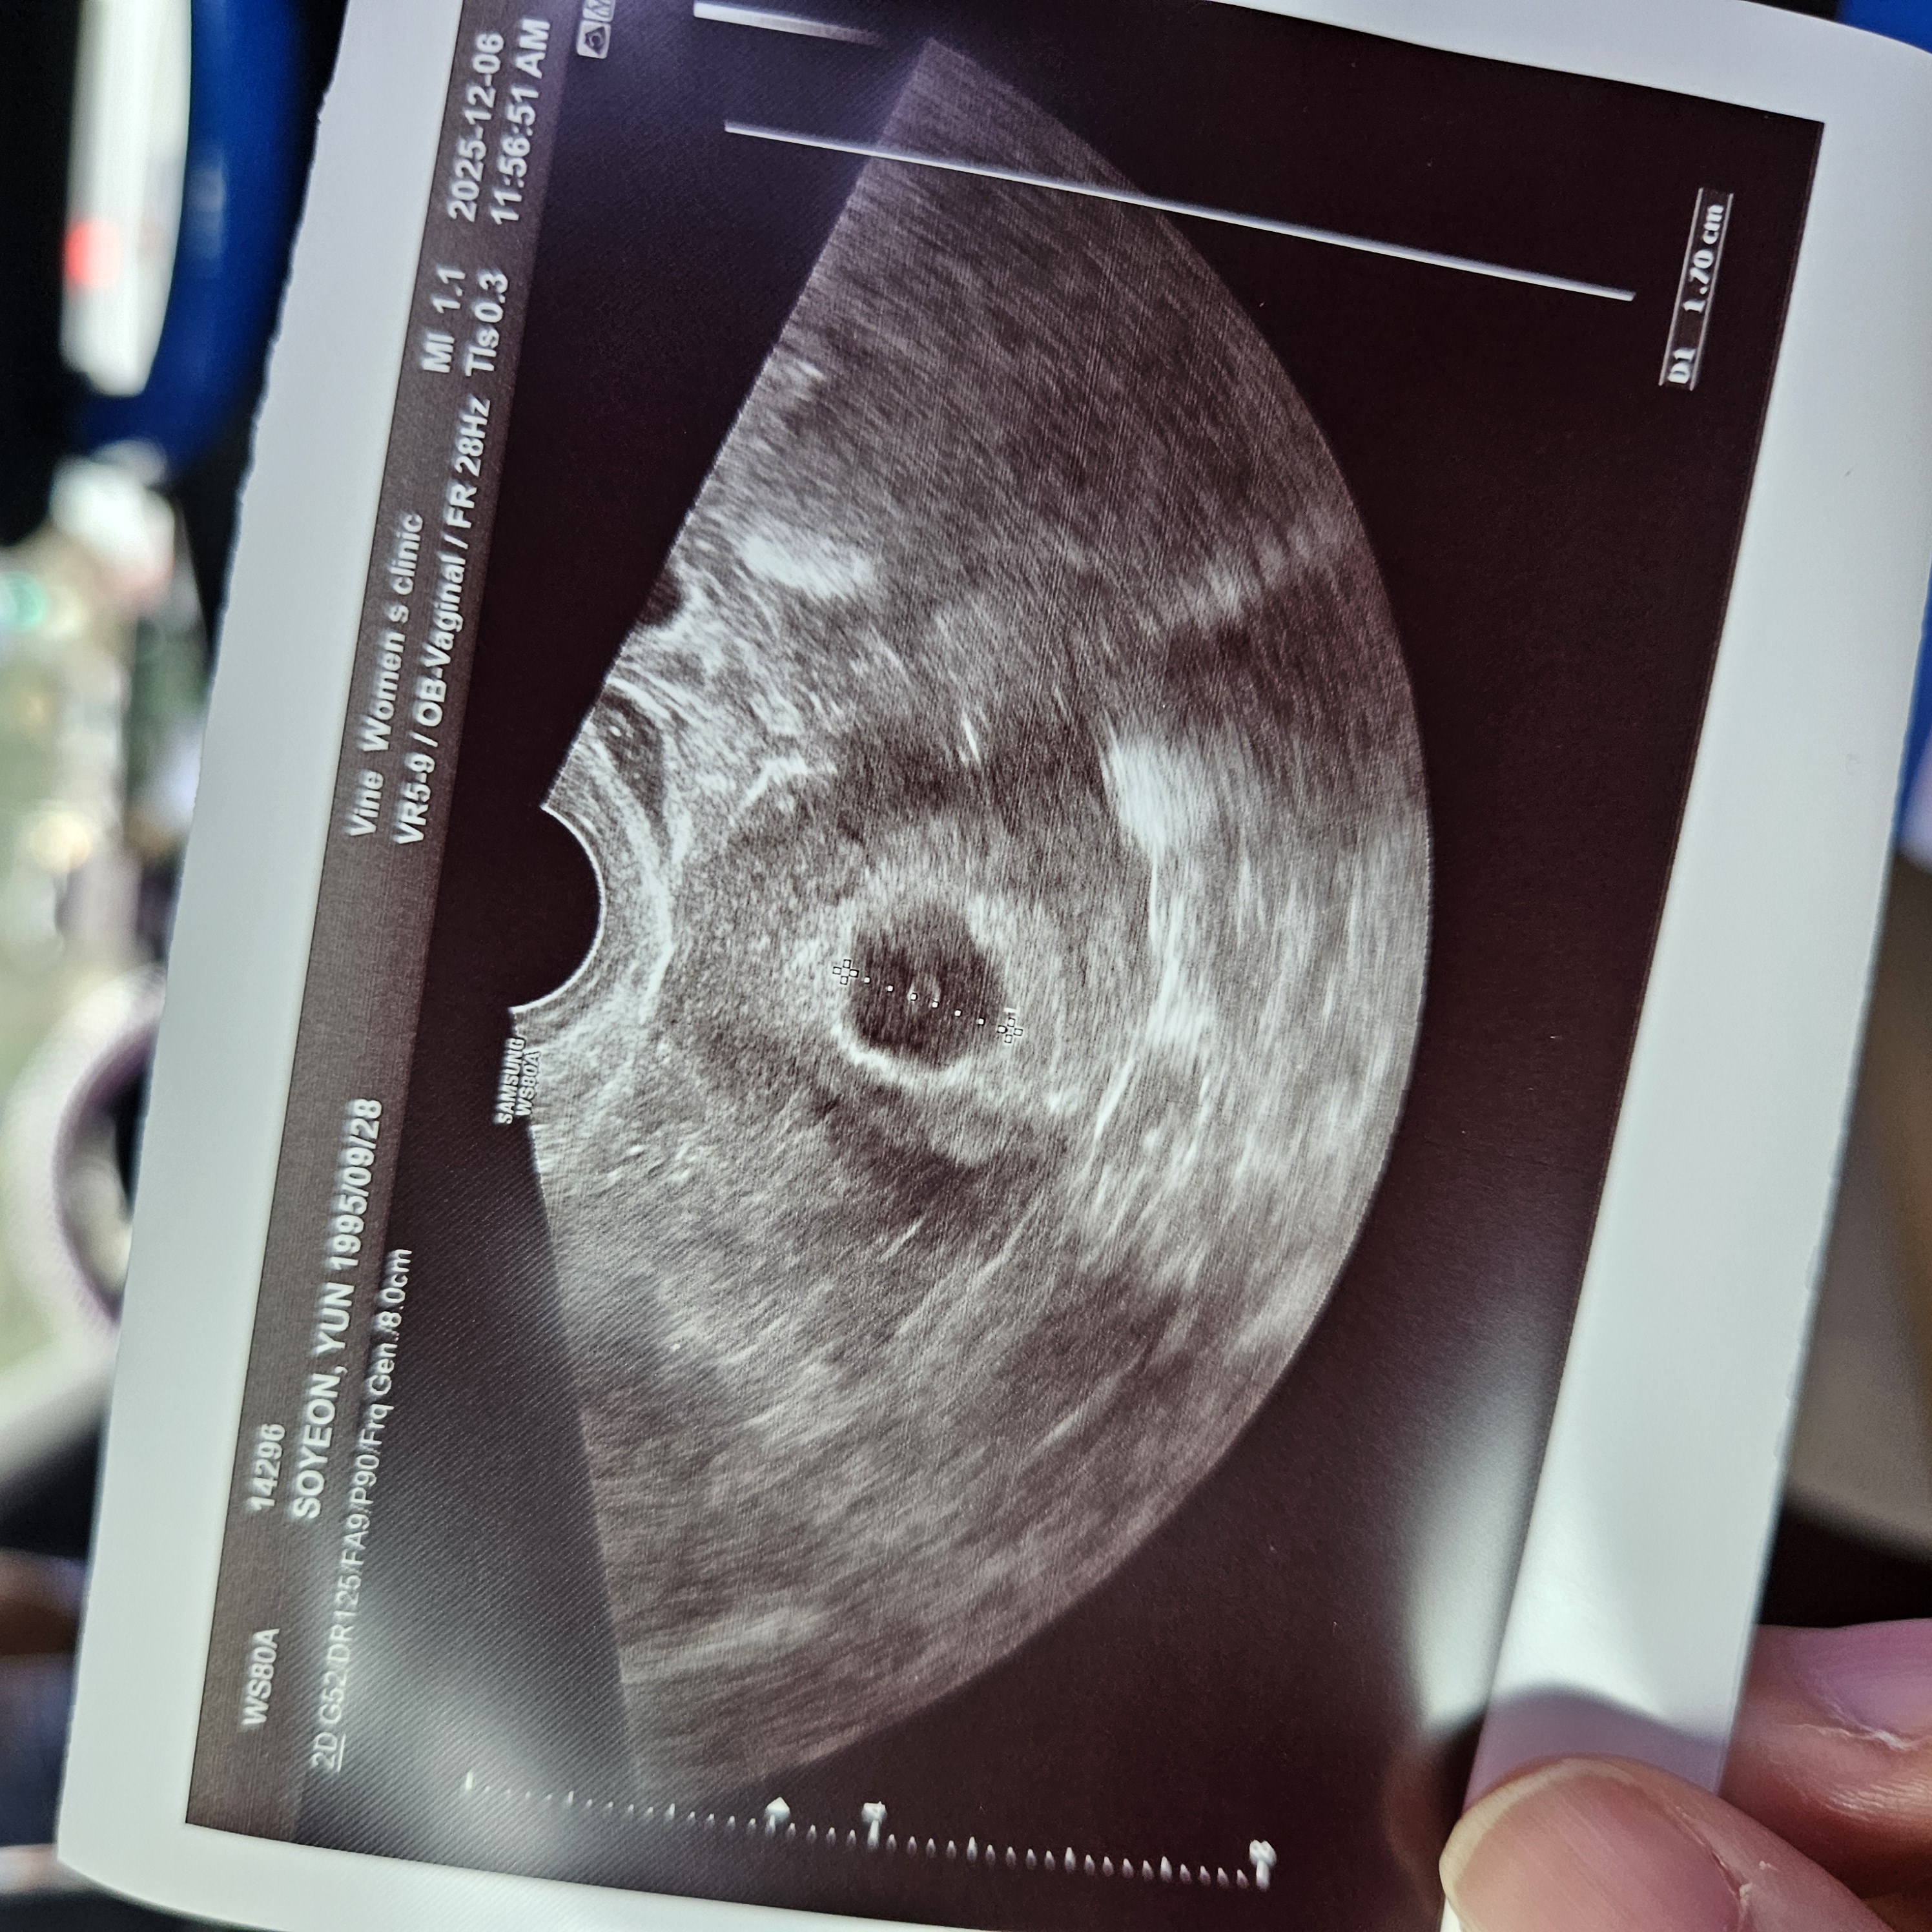

임신 5주차5일정도되었고 제가 눈오는날 추운 차에 5시간이나 갇혀있었는데 다음날 바로 피가나오더라구요ㅠㅠ 병원에선 피고임이 살짝있지만 문제는 없다고 하시긴했는데 한 3일째 조금씩 피가 나오니까 걱정되네요 갈색혈 있을때는 그냥 눕눕하고있는게 가장 좋을까요?? 누워있을때 안좋은 자세가 있나요??

병원에서 따로 처방은 없으셨나요? 사실 누워만 있어도 나올 피는 나오긴하지만 누워있으면 흡수되는데 도움이 되긴해요. 전 4주 6일부터 8주 4일까지 피비침 있었는데 얼마 전 10주 진료 잘 받고 왔어요.